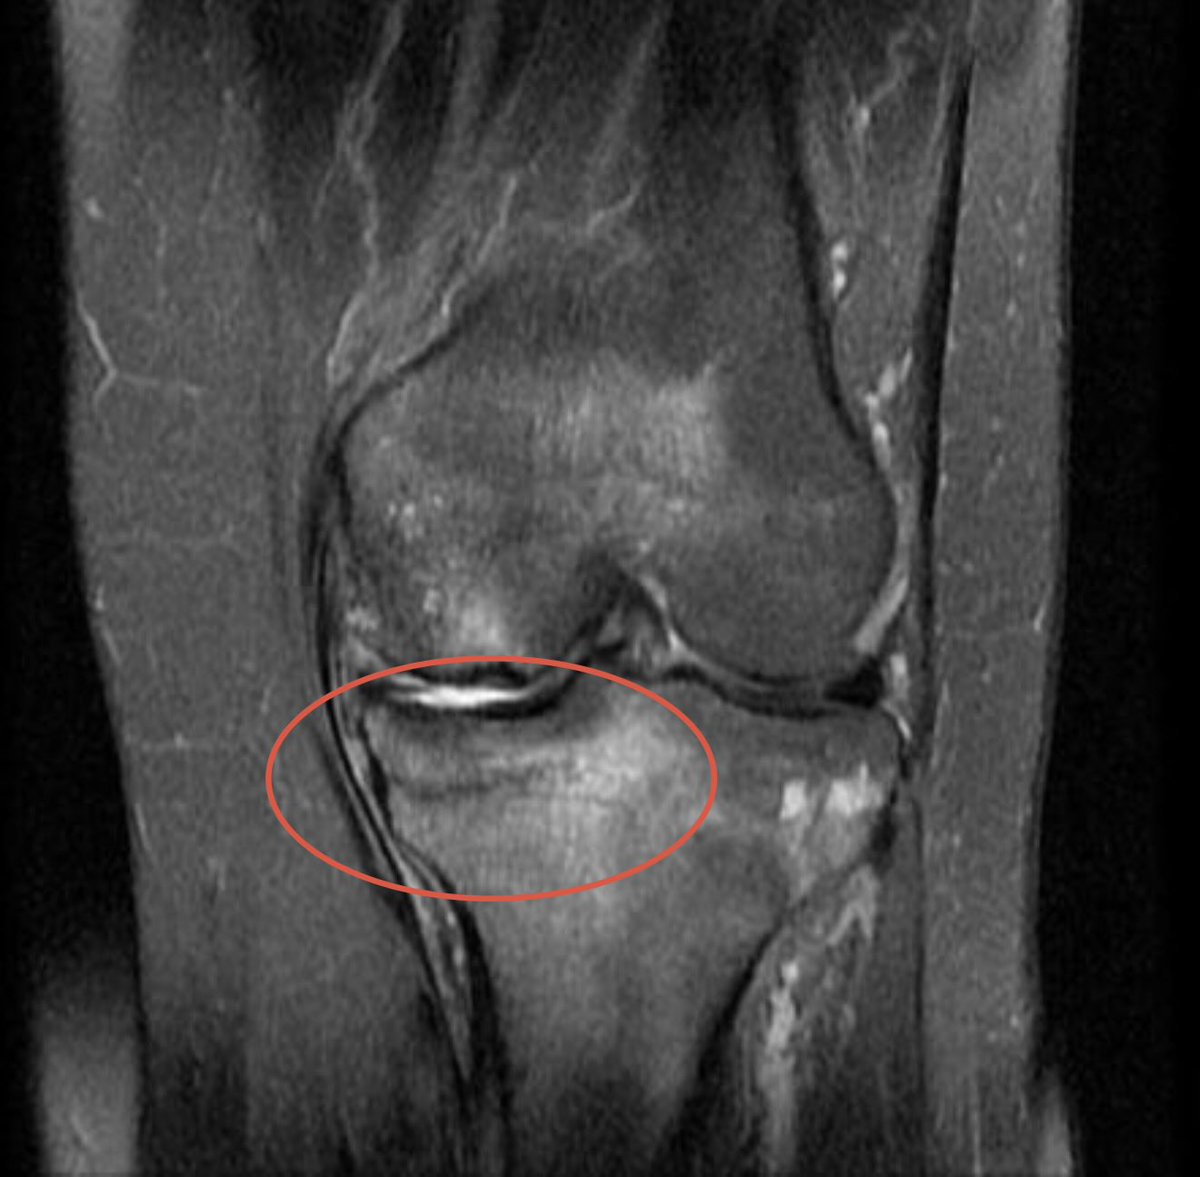

Maxx Crosby is eight weeks from having meniscus surgery and got off crutches only last week. He is on schedule, and they are working to get him ready for the regular-season opener. Here is what Crosby’s knee surgeon, Dr. Neal ElAttrache, said to ESPN this morning: “Maxx Crosby is doing very well in the early part of his rehab and recovery from surgery to treat a significant meniscus tear and the related stress injury to the bone and cartilage in his knee. He is certainly on track in his planned program….he feels very well and is already much improved compared to before surgery. “We truly respect the work of the Ravens staff with Maxx regarding the contract physical exam. We also understand the challenge the staff faces when tasked to provide a future risk assessment based on an evaluation early in the recovery process. This is especially challenging when dealing with an elite player like Maxx considering the level of commitment necessary for a team to obtain him. The timing of this assessment is unfortunate because the apparent risk will lessen as his recovery progresses and his return to performance over the next few months becomes clear. “At this point, Max is doing an excellent job attacking his rehab and his knee is responding very well. We look forward to Maxx returning to his elite level of performance this season as planned and for several more to come.”